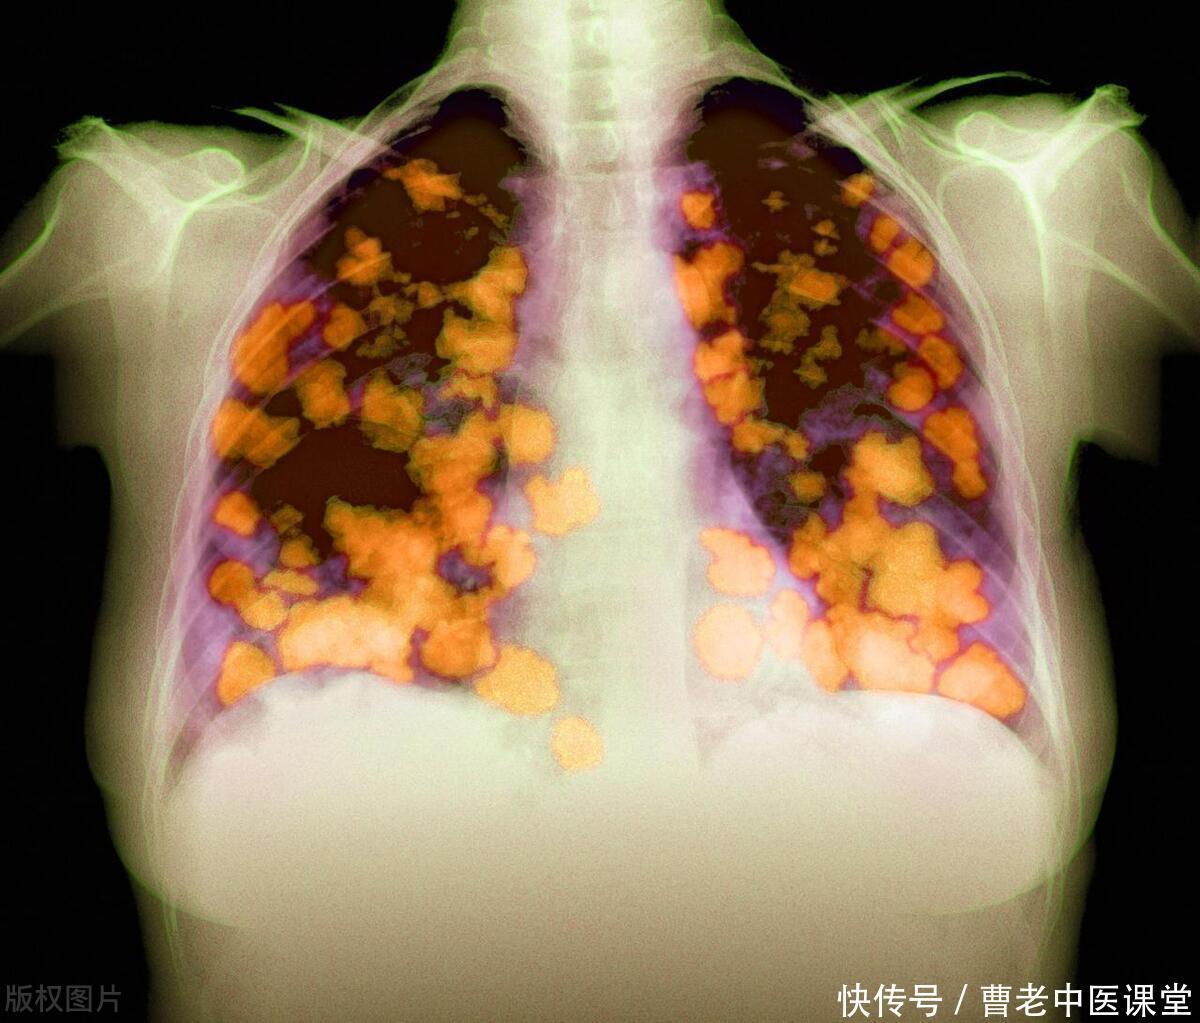

氡气被确定为肺癌的主要致病因素,氡气又是在哪些地方有呢?